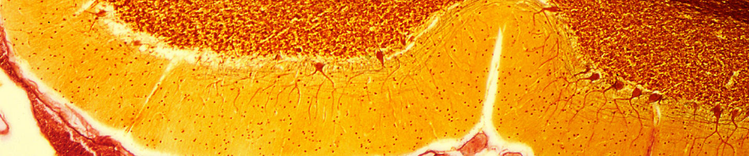

小脑中的浦金野细胞